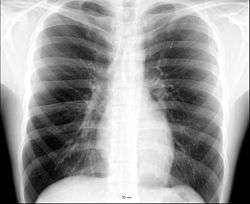

The thorax or chest (from the Greek θώραξ thorax "breastplate, cuirass, corslet"[1] via Latin: thorax) is a part of the anatomy of humans and various other animals located between the neck and the abdomen.[2][3] The thorax includes the thoracic cavity and the thoracic wall. It contains organs including the heart, lungs, and thymus gland, as well as muscles and various other internal structures. Many diseases may affect the chest, and one of the most common symptoms is chest pain.

Different types of diseases or conditions that affect the chest include pleurisy, flail chest, atelectasis, and the most common condition, chest pain. These conditions can be hereditary or caused by birth defects or trauma. Any condition that lowers the ability to either breathe deeply or to cough is considered a chest disease or condition.

The major pathophysiologies encountered in blunt chest trauma involve derangements in the flow of air, blood, or both in combination. Sepsis due to leakage of alimentary tract contents, as in esophageal perforations, also must be considered. Blunt trauma commonly results in chest wall injuries (e.g., rib fractures). The pain associated with these injuries can make breathing difficult, and this may compromise ventilation. Direct lung injuries, such as pulmonary contusions (see the image below), are frequently associated with major chest trauma and may impair ventilation by a similar mechanism.